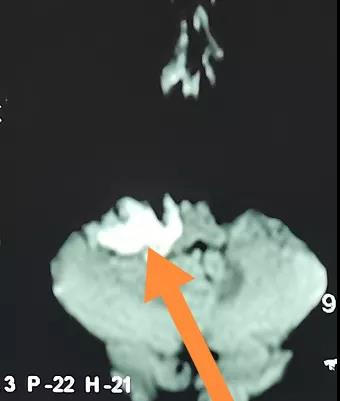

根据结果显示,肿瘤位于右侧桥小脑角区,边界不规则,MRI增强检查,肿瘤无强化,DWI上呈高信号,CT骨窗内听道无明显扩张,初步考虑为右侧桥小脑角表皮样囊肿,需要手术治疗。

主要应与该区的蛛网膜囊肿和明显囊变的听神经瘤区别。桥小脑角区蛛网膜囊肿少见,形态规则,弥散加权成像上呈低信号,而颅内表皮样囊肿形态不规则,沿周围脑池生长,在弥散加权成像上呈高信号。明显囊变的听神经瘤在增强扫描时襞壁和残留的肿瘤实质强化,而表皮样囊肿不强化。弥散加权成像对区别明显囊变的听神经瘤和表皮样囊肿也很有效,听神经瘤的囊性部分在弥散加权成像上呈低信号,而表皮样囊肿呈高信号。